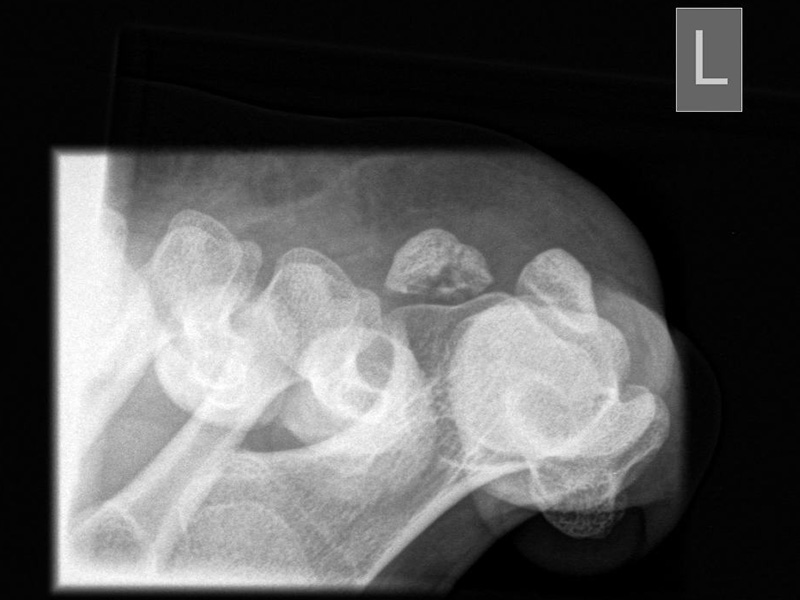

ap (anterior - posteriore) axiale Aufnahme der Sesambeine

Positionierung:

• Patient in Rückenlage, Ferse auf der Filmplatte liegend.

• Sprunggelenk in 15°-Spitzfußstellung.

• Maximale Dorsalextension der Zehen mit einer Schlaufe.

• Zentralstrahl fokussiert auf das Großzehengrundgelenk.

• Röntgenröhre 0° vertikal.

• Filmposition horizontal.

Kennzeichen des Röntgenbildes:

• Tangentiale Abbildung des Sesambeingleitlagers.

• Pathologien der Gleitrinne sind gut erkennbar.

• Dislokation der Sesambeine aus der Gleitrinne sind gut erkennbar.

Besondere Anmerkungen zum Beispielbild:

• Fragmentationsstadium bei Osteonekrose des lateralen Sesambeins.

• Beide Sesambeine sind in der Gleitrinne zentriert.

Zur Vollansicht und zum Lesen der Bildbeschreibung bitte die Bilder anklicken.